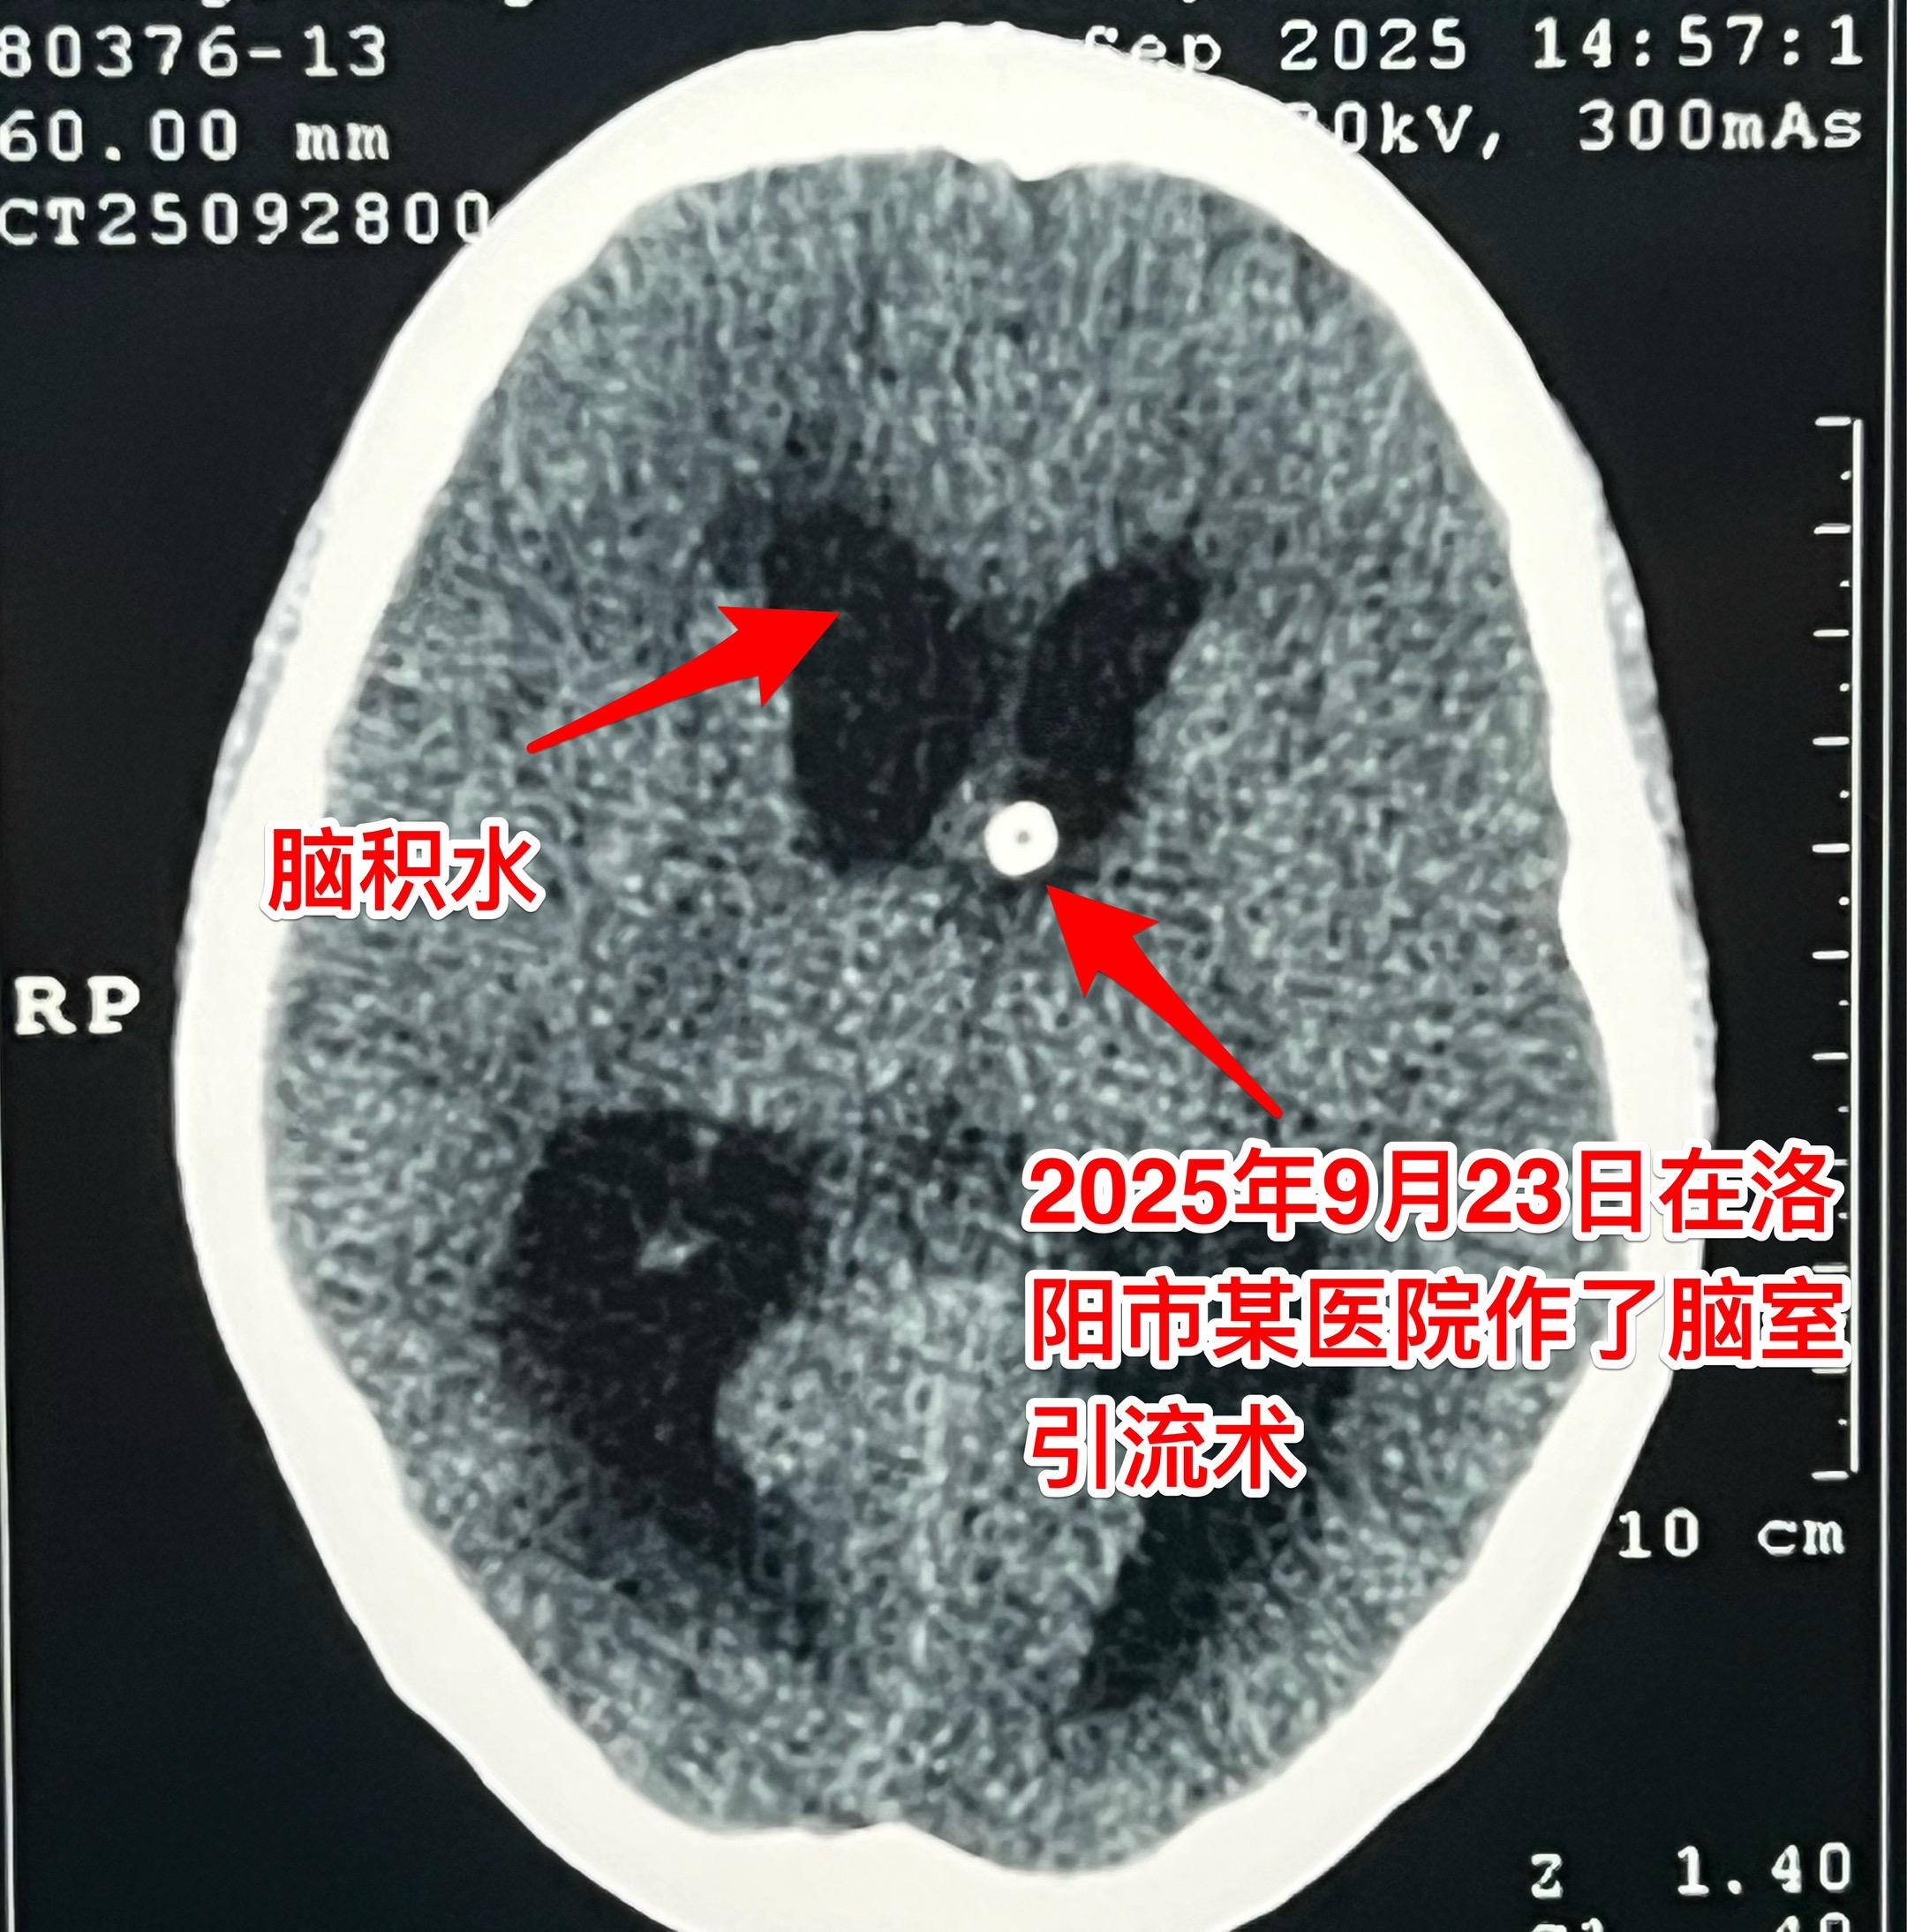

颅咽管瘤的症状科普。之前我多次讲过颅咽管瘤的症状,结合这个病人再说一次...

常规一天两个颅咽管瘤手术。今日两个颅咽管瘤手术。 上午...